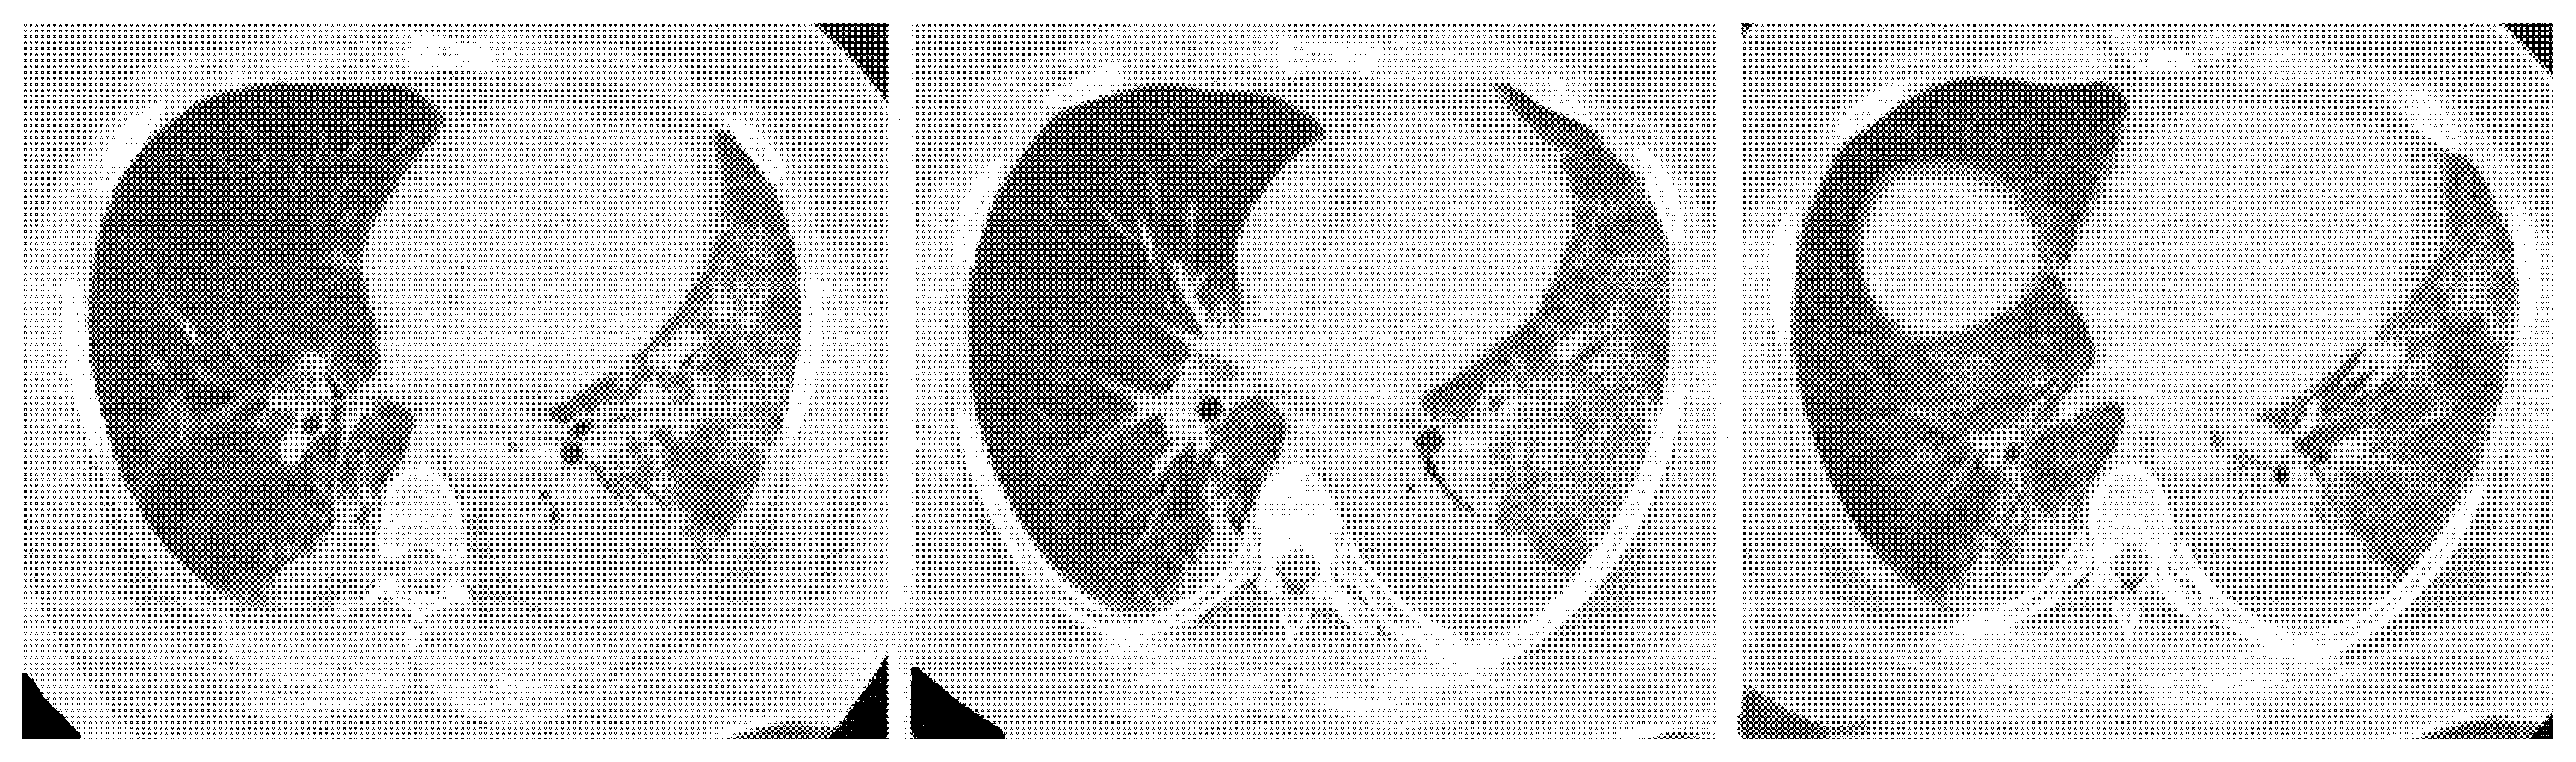

| Lesions | GGO, reticulations, consolidations | consolidations, GGOs | |

| Distribution | Homogeneous; lower lung lobes, along bronchovascular bundles and lung periphery; loss of volume of lower lobes | Patchy; peripheral lower lobes or along the bronchovascular bundles | |

| CT pattern | NSIP OP NSIP-OP UIP DAD-unclassifiable | 50% 20% 25% 10% +/− | 20% 50% 25% <5% ++ |